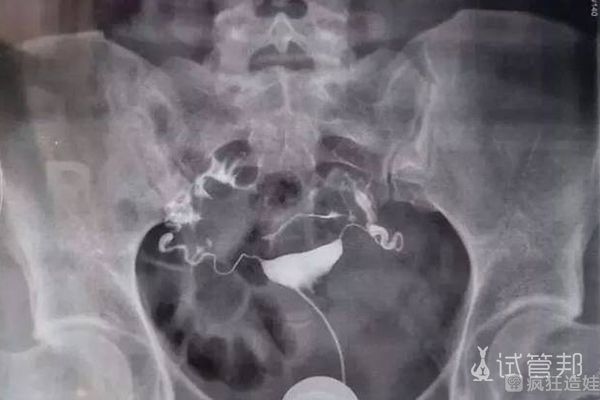

取卵后就可以等待胚胎移植了。其实我在取卵后感觉真的很不舒服,而且出现了腹水症状。在家呆了整整一周,一个星期后就好了。子宫检查显示有少许粘连,因此我又进行子宫粘连手术。其实还是因为年龄比较大了,然后身体各方面都不行了,出现各种问题。我等月经大概等了半个多月。还是去医院打了催经针,月经才来。